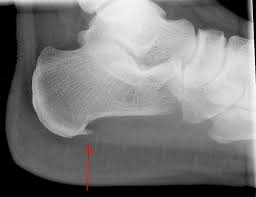

구조적으로 발바닥의 아치가 정상보다 낮아 흔히 평발로 불리는 편평족이나, 아치가 정상보다 높은 요족(cavus) 변형이 있는 경우 족저근막염의 발생 가능성이 높다. 또한 다리 길이의 차이, 발의 과도한 회내(발뒤꿈치의 바깥쪽 회전과 발목의 안쪽 회전의 복합 운동) 변형, 하퇴부 근육의 구축 또는 약화 등이 있는 경우에도 족저근막염을 유발할 수 있다. 족저근막의 발뒤꿈치뼈 부착 부위에 뼛조각이 튀어나온 사람들 중 일부에서 족저근막염이 발생하기도 한다.